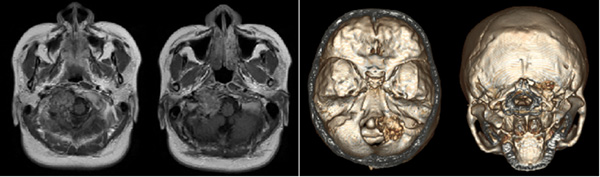

检查时,医生在小兰颈枕交界的枕髁区发现了一种少见的肿瘤,初步考虑是骨/软骨肉瘤,一种常见于儿童及青年长骨干骺端的原发性恶性肿瘤。这种肿瘤很少累计颅骨,而小兰的肿瘤则生长在头颈交界区(头部与脖子连接的区域),已经压迫到了椎动脉以及后组颅神经,引起了她的伸舌右偏以及声音嘶哑。考虑到手术切除肿瘤可能会影响头部稳定性,严重的话甚至可能危及生命。小兰选择暂缓手术、留下自己的孩子,等待分娩结束后再行手术治疗。

十月怀胎,一朝分娩,小兰生下了一个健康的宝宝,可难题又来了。因为小兰的肿瘤位于颅底、位置较深。已经严重破坏了枕髁区的骨质,与供应脑干的血管边界不清。术中将面临肿瘤切除困难、颅神经损伤、椎动脉破裂大出血以及颈枕部不稳定等多重困难。

术后第二天,小兰已经可以下地活动和正常进食了,咳嗽反射也表现良好。术后复查头CT、MRI及颈部平片示术区无出血、肿瘤完整切除;枕颈固定装置位置及颈椎曲度均良好。